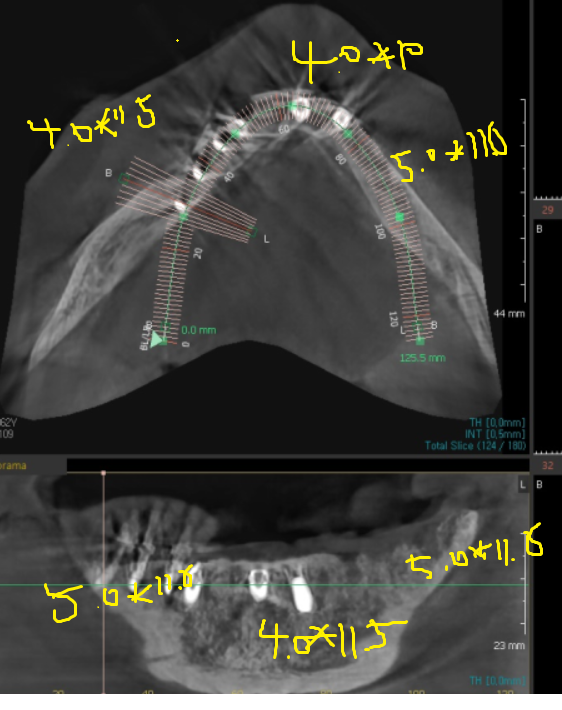

윗니 어금니는 ct를 통해 남아있는 뼈를

분석하였습니다.

미리 네비게이션 기술을 활용하여

수술 식립 각도, 사이즈를 분석했습니다.